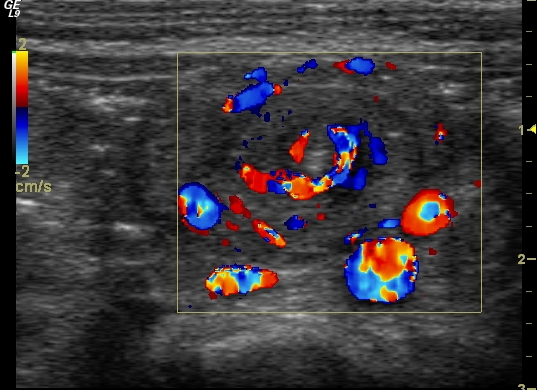

Vesicouretral (VU) reflux. Reflux stands for the reentry of urine from the bladder to the ureter and the collecting system of the kidneys due to the insufficiency of the uretrovesical valve. This can lead to a transient or a permanent dilatation of the urinary tracts. US can only raise suspicion for UV reflux through indirect signs such as thickened pyelon wall, small kidney, thinner and blurry cortico medullary junction, uneven parenchyma, thickened bladder wall. Reflux can be depicted with MCU or sonocystogrphy. Reflux is internationally categorized in 5 levels (I-V). Its special form is the intrarenal reflux that appears in the upper or lower pole of the kidney.

Image

24.a.

24.b.

24.c.

24.d.

24.e.

Miction cystourethrography. a. Reflux in the left normal diameter ureter.VUR l.s. Gr.I. b. Both ureters have a normal diameter as they refill with the contrast material refluxing from the bladder. VUR l.u. Gr.II. c. There is a slightly dilated right ureter and collecting system in the right kidney, the calices are widened. VUR l.s. Gr.III. d. Dilated ureter and collecting system can be seen on the left side. VUR l.s. Gr. IV. e. The right ureter is markedly dilated and elongated the pelvicalyceal system is also markedly dilated, the calices are rounded, contrast material appears in the tubules as well. VUR l.d. Gr.5. with intra-renal reflux.